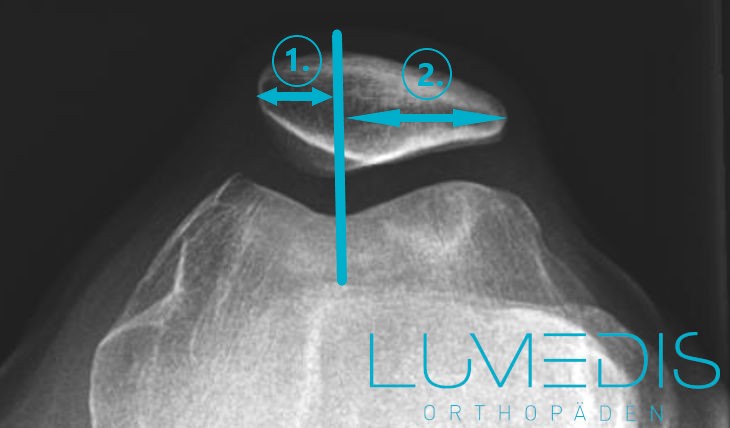

Röntgenbild Defilee der Kniescheibe bei Patellalateralisation

Das Gleitlager (Trochlea) wird symmetrisch geteilt.